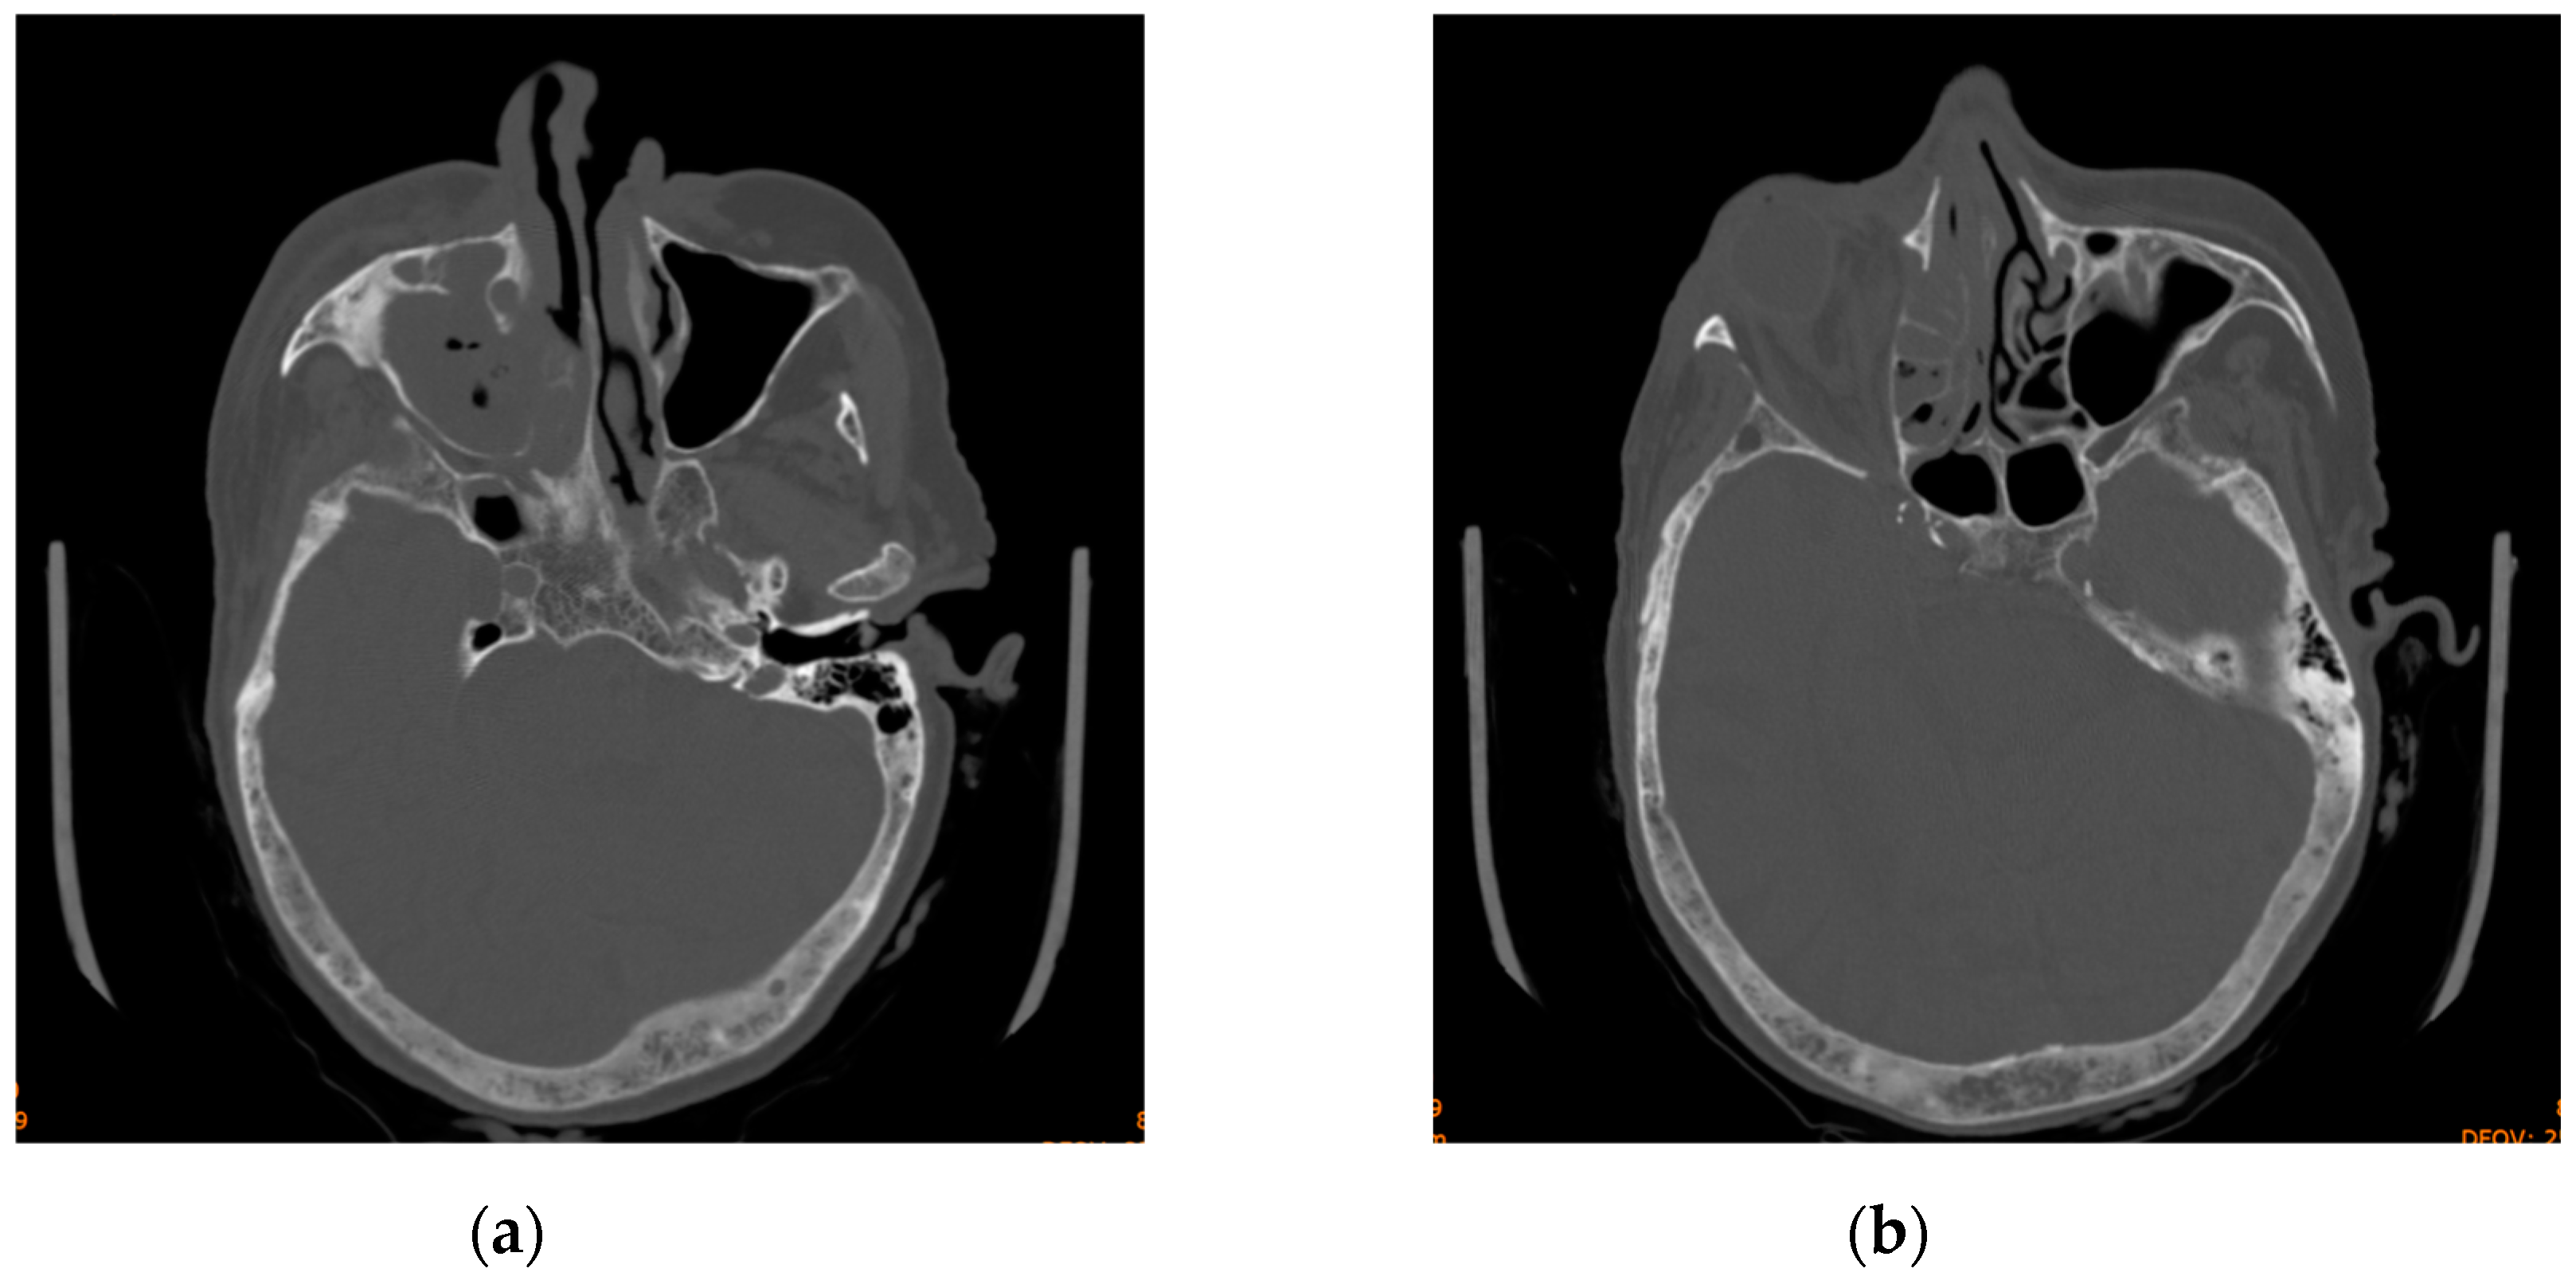

2. Case 1

3. Case 2